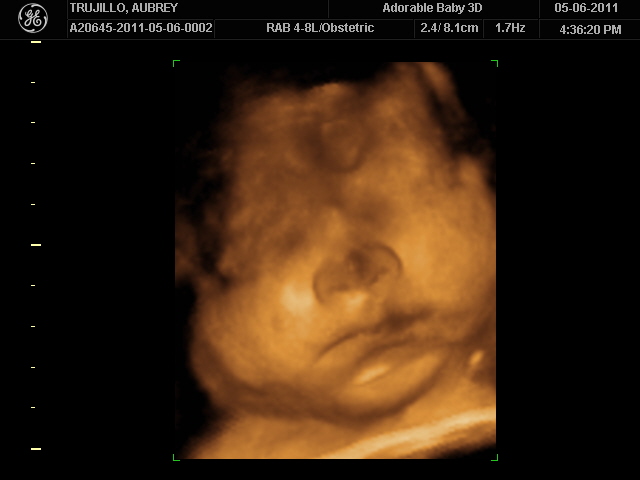

20 weeks - profile20 weeks - Profile again20 weeks - Right foot!20 weeks - sucking thumb!!!!20 weeks - hand near face20 weeks - flexing his bony arms!20 weeks - hiding from mommy and daddy!20 weeks - it's a boy!33 weeks - 3D!33 weeks - 3D!33 weeks - 3D!